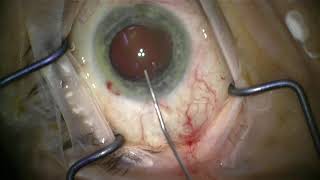

Dr Cronin provides these videos as an educational resource for training ophthalmologists, other ophthalmologists and patients. Dr Cronin specialises in corneal and anterior segment diseases including LASIK, laser eye surgery, cataracts, keratoconus, Fuchs endothelial dystrophy and pterygium surgery.